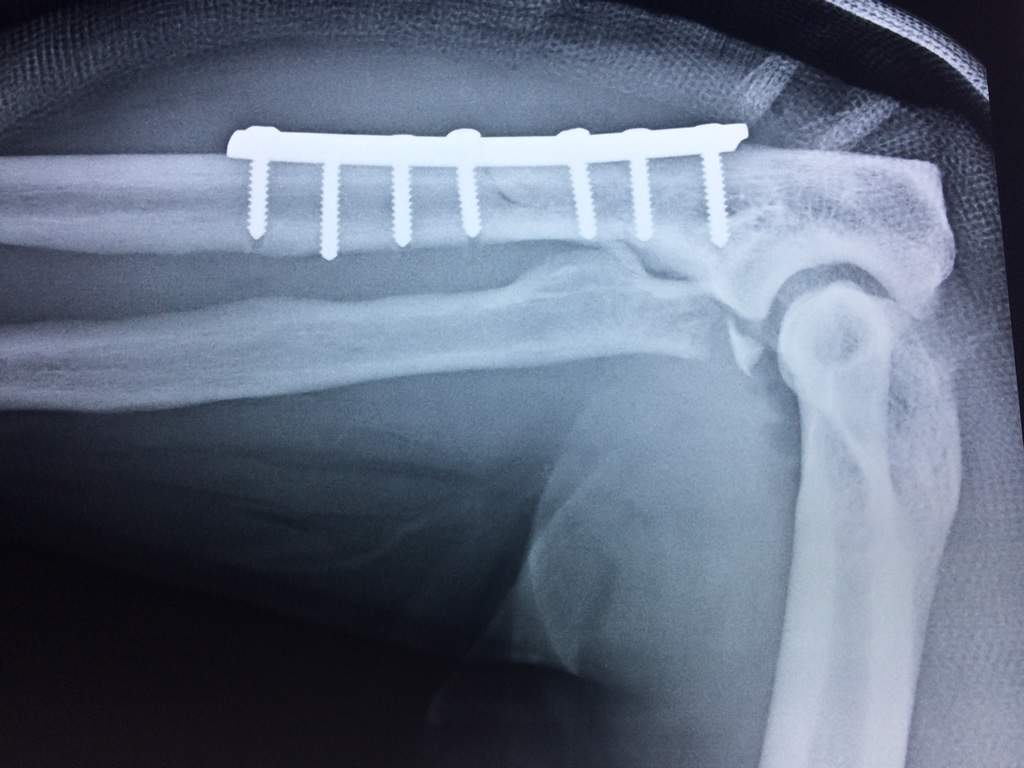

Cirugías de Calcaneo - Codo

En anatomía humana, la articulación del codo es la que une el brazo con el antebrazo, conectando la parte distal del hueso húmero con los extremos proximales de los huesos cúbito y radio.

La articulación principal que constituye el codo se denomina humero radio-cubital y puede dividirse en dos partes bien diferenciadas, la articulación humero-radial y la humero-cubital.

Por otra parte el cúbito y el radio forman también una articulación entre si en las proximidades del codo, la cual se denomina articulación radio-cubital proximal.